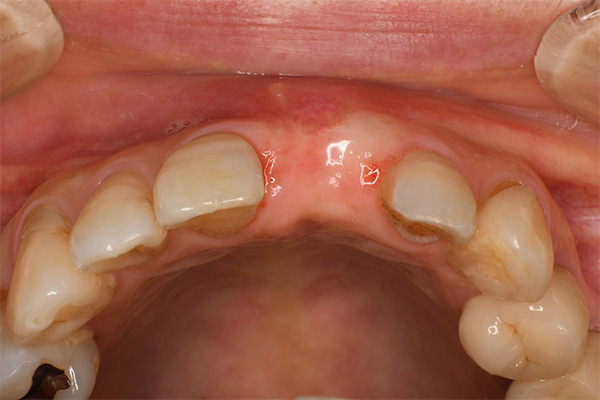

抜歯9ヶ月後(左)歯肉にヘコみができているので手術で歯肉を増大させる

2週間後、赤みは残るが歯肉の厚みは増えた(右)